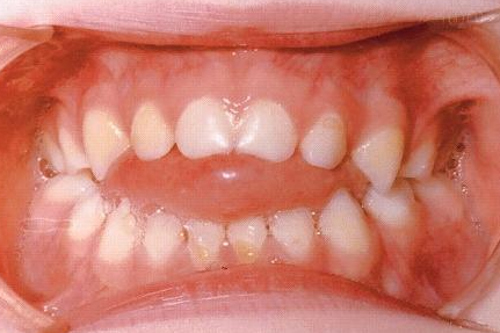

Прикусы, когда нужна ранняя коррекция, это — открытый прикус, перекрестный и обратный (мезиальный) прикус.